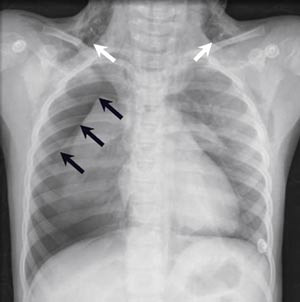

Under et kraftig hosteanfall senere på kvelden utviklet hun i løpet av få sekunder betydelig subkutant emfysem over hele halsen. Etter noen minutter spredte emfysemet seg opp mot høyre kinn og øye. Oksygenmetningen sank i løpet av noen minutter og røntgen thorax viste høyresidig pneumothorax og pneumomediastinum (fig 1). Det ble lagt inn thoraxdren.

Hos denne pasienten kunne emfysemet gi ytterligere kompresjon av luftveiene og dermed forklare den synkende oksygenmetningen. I en situasjon preget av akutt respirasjonssvikt må imidlertid lungene undersøkes med tanke på akutt patologi som pneumothorax, fortetninger i bronkialtreet eller hevelse/infiltrater i lungeparenkymet. Ved påvist pneumothorax er det indikasjon for dreninnleggelse hvis avstanden mellom lunge og ytre pleura er om lag 2 cm eller mer samtidig som respirasjonen er klinisk besværet og oksygenmetningen redusert. Hos pasienter som har pådratt seg pneumothorax etter barotraume, er det nesten alltid indikasjon for drenasje uavhengig av pneumothoraxens størrelse og de kliniske funnene.